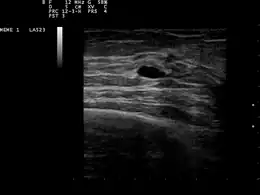

La présence et la nature d'un kyste peuvent être confirmées par une échographie, une biopsie à l’aiguille fine (extraction du contenu par une aiguille)[4] ou une mammographie. L'échographie peut montrer si le kyste contient des nodules solides, un signe qu'il peut être pré-cancéreux voire cancéreux. Un examen de cytologie pathologique des liquides extraits du kyste peut aussi aider au diagnostic, notamment s'il contient du sang.

Une patiente présentant des symptômes d'un kyste passe une mammographie de diagnostic, même s'il n'y a pas de suspicion de cancer du sein. Ce type de mammographie s'accompagne de la possibilité de pratiquer une échographie mammaire. Dans le diagnostic d'un kyste mammaire, l'échographie est privilégiée et considérée comme fiable à 95% voire 100%. Elle fournit une image précise de l'apparence du kyste (simple ou complexe) et peut aussi distinguer une bosse solide d'une poche remplie de liquide, ce pour quoi une simple mammographie n'est pas suffisante[5].